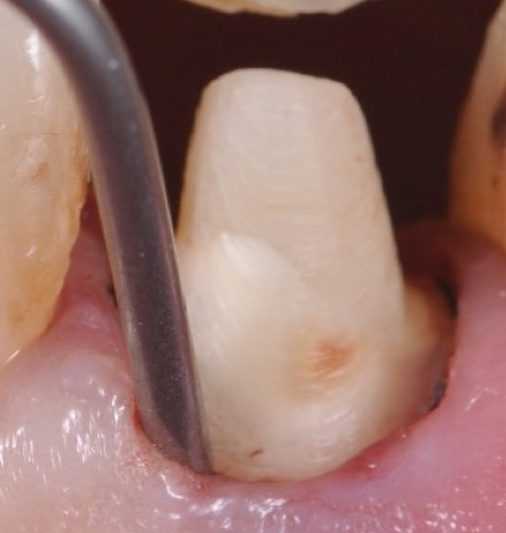

(Рис.2)

(Рис.3)

(Рис.4)